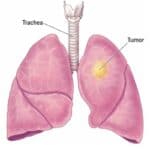

U Phổi | Bài giảng CĐHA

U phổi (Lung Tumors) là bệnh lý thường gặp. Ung thư phổi là nguyên nhân tử vong hàng đầu ở các nước công nghiệp phát triển. Ung thư phổi là loại ung thư đứng hàng thứ hai tại Mỹ nhưng tỷ lệ tử vong lại đứng hàng đầu. Tử vong do ung thư phổi nhiều hơn số tử vong do ung thư vú, tiền liệt tuyến và đại trực tràng cộng lại…